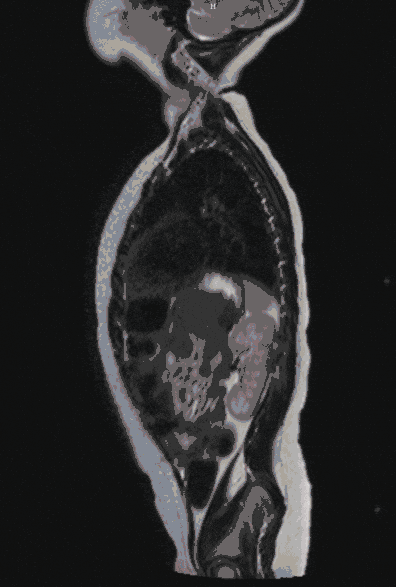

Spina Bifida

Clefts of the spinal cord, its sheaths and bony structures (spina bifida) occur rarely nowadays. The prognosis correlates primarily with the extent of a neurological disorder.